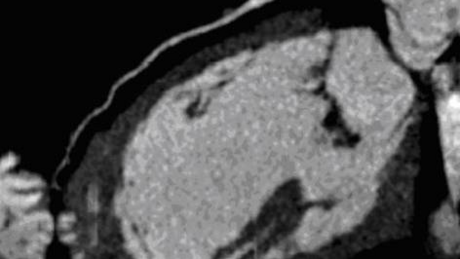

Bild 1-3: Darstellung einer Herzmuskelentzündung bei drei verschiedenen Patienten.

Der Herzmuskel ist jeweils dunkel, die entzündeten Areale kommen durch die Kontrastmittelanreicherung hell zur Darstellung.